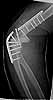

I revised the failed fixation in Nov. 2003. Please see attached file (first revision). The triceps was mangled with its central portion very deficient. I used an olecranon osteotomy.

first revision